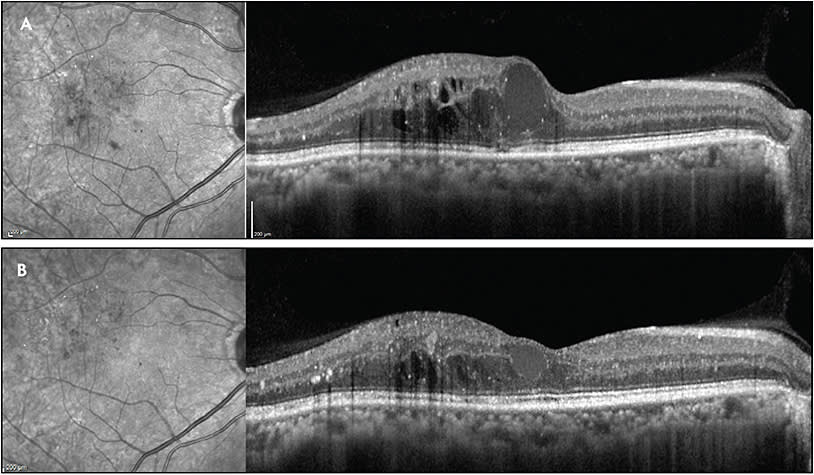

More recently, newer modes of laser retinal therapy, best termed low-intensity photo stimulation (LIPS), involve grid type application of nonphotocoagulative laser spots to “photostimulate” outer retinal tissues, primarily the retinal pigment epithelium (RPE), to either increase production of metabolites that inhibit neovascularization and reduce vascular permeability activity or to downregulate production of mediators that increase vascular permeability and neovascularization (Figure 2).20-27 To qualify as LIPS, a laser treatment session must not result in any detectable outer retinal or RPE damage on current imaging modalities such as fundus photography, angiography, autofluorescence, or optical coherence tomography. With this type of “subthreshold” laser, many of the benefits of CW lasers are theoretically obtained without the adverse side effects. Several laser manufacturers offer LIPS lasers systems, which include Micropulse and Endpoint Management (Iridex), Smartpulse (Lumenis), Easyret in subliminal mode (Quantel Medical), Navilas Microsecond Pulse (OD-OS), 2RT (Ellex), SP-Mode (Lightmed), and LPM (Nidek), all of which can be safely applied near the fovea without visible damage when used according to published safety protocols. There have been several small, uncontrolled studies that have shown the benefits of LIPS lasers in treating DME either alone or in combination with pharmacotherapy, yielding results comparable to those obtained with conventional laser but with no tissue damage or scotomas.18,19,28-44